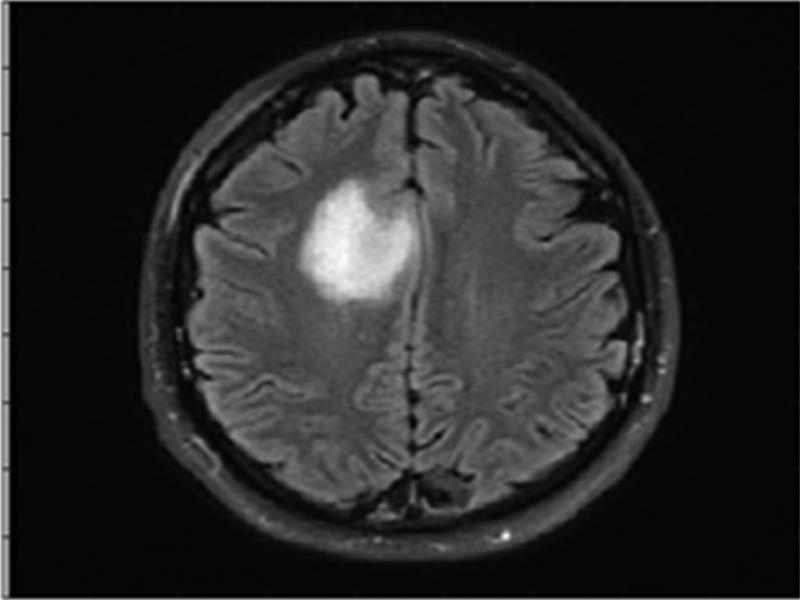

The outcome of the proposed methodology is seen in figure 9. Figure 8 represents the input image and figure 9 is the processed image with the highlighted tumor region.

Figure 8:

Input image.

A distinct highlighted tumor region is visible in the final output image.